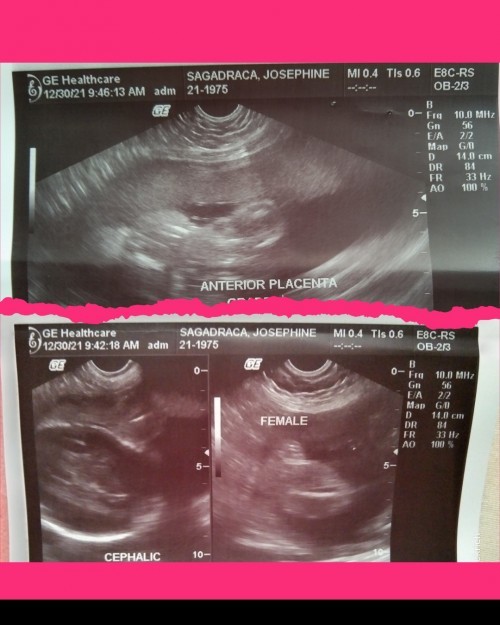

25 weeks na po baby ko .. kita nadin po gender niya 🥰

25weeks 773 grams bby ko ewan kulg ngayong 6months ako.